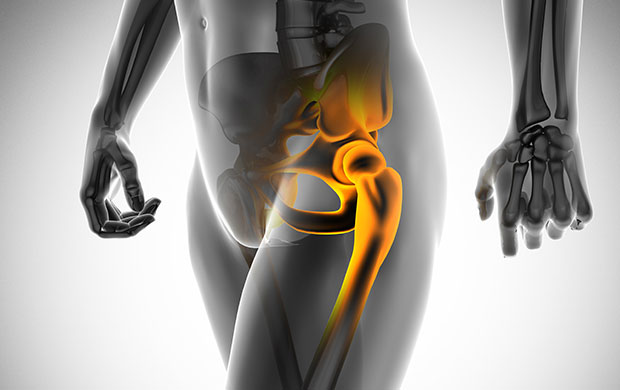

고관절 통증 증상(엉덩관절)은 오른쪽과 왼쪽의 골반과 넙다리뼈가 연결된 관절의 통증을 일컫습니다. 고관절은 상체의 하중을 분산시키는 역할을 하며, 일어서거나 앉거나 일상생활에서 자주 쓰이는 관절이며 부담도 잘 받게 됩니다. 모양도 크기도 탁구공만 합니다. 일상적으로 걸을 때 고관절에 체중의 3~4.5배의 무게가 실리게 됩니다. 계단을 오를 때는 대퇴골두에 전해지는 무게는 몸무게의 8배, 달리는 경우 10배에 가까운 하중을 견뎌내애 한다고 합니다. 탁구공 크기만 한 대퇴골두가 감당하기에는 너무 무겁기 때문에 고관절이 느끼는 부담도 크고 쉽게 손상될 수 있습니다. 다른 관절과 마찬가지로 감당하기 어려운 충격이나 무게가 가해지면 고관절 통증 증상이 발생하게 되는데요. 퇴행성 고관절염, 대퇴골 골절, 대퇴골두 무혈성 괴사, 선천성 고관절 탈구 등이 대표적인 고관절 통증 질환입니다.